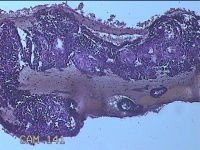

性别

女

年龄

35岁

临床诊断

人流不全

一般病史

人流术后41天。

标本名称

宫腔内容物

大体所见

灰白暗红色不规则碎组织1.8x1.5x0.3cm一堆,未发现明显的绒毛样组织。